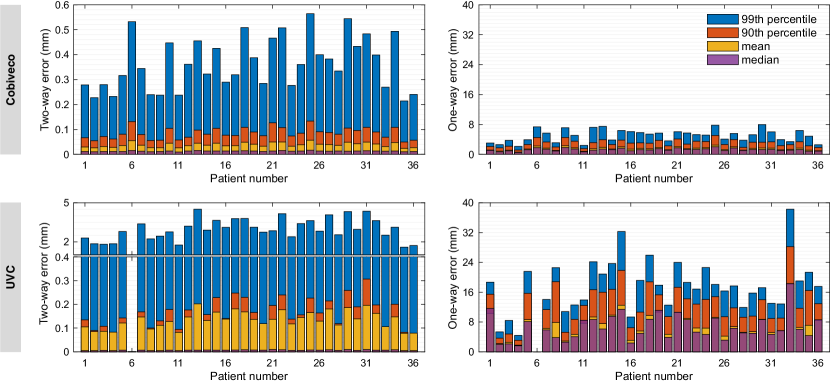

The transfer errors as defined in section 3.3 were computed for all patient geometries as well as both possible directions. To condense the results, we averaged the error histograms across all geometries and both directions. This leads to an equal weighting of errors for each case, independent of the number of nodes in the respective mesh. The average histograms are depicted in Fig. 15. Statistical measures (vertical lines) of the average histograms are given in Table 1.

The two-way error shows a 3.5-fold improvement of the mean and the 99th percentile is reduced even more. However, the median is increased, which indicates that there are more small (), but fewer large errors than for UVC. With a mean value well below one mean edge length, our two-way errors for UVC are comparable to those in [2].

The one-way error is more relevant in practice as it goes beyond evaluation of interpolation errors. Here, the error histogram decays much faster for Cobiveco and all statistical measures show a more than 4-fold improvement compared to UVC. In particular, the mean one-way error is reduced from 7.1 to 1.5 mm and the 99th percentile is reduced from about 24 to 6 mm.

Fig. 16 shows transfer errors for each individual patient geometry. In all patients, the 99th percentile of the two-way error for Cobiveco is below the mean edge length, which is not the case for UVC (note the broken y-axis). For one-way errors, the largest 99th percentile in a single patient is about 8 mm for Cobiveco and 38 mm for UVC.

To assess the spatial distribution of transfer errors, we visualized their mean across all patients on the mean shape of the SSM. To avoid artifacts due to spatial interpolation, only errors directly available on the mean shape of the SSM were taken into account for this purpose, i.e., only one transfer direction was included.

The result in Fig. 17 (left) clearly shows that the two-way errors for UVC concentrate at discontinuities of the coordinates (compare with Fig. 1). Furthermore, there are large errors at the singularities of the rotational coordinate. For Cobiveco, these errors are greatly reduced, because only the transventricular coordinate is discontinuous and the origin of the apicobasal coordinate coincides exactly with the rotational singularities. Choosing narrower colormap limits to visualize the two-way errors for Cobiveco (Fig. S5) reveals the pattern of the isocurves used to compute the apicobasal coordinate (Fig. 13, bottom-left). These many non-zero, but still small errors explain the slight increase in the median two-way error observed for Cobiveco.

For the one-way error (Fig. 17, right), the discontinuities and singularities only play a minor role. It is dominated by inconsistencies of the coordinates across different geometries, which lead to inconsistent point correspondences. On average, the largest one-way errors occur at the RV outflow tract for Cobiveco and at the apical region of the LV lateral wall for UVC. Nevertheless, absolute errors are much smaller for Cobiveco.